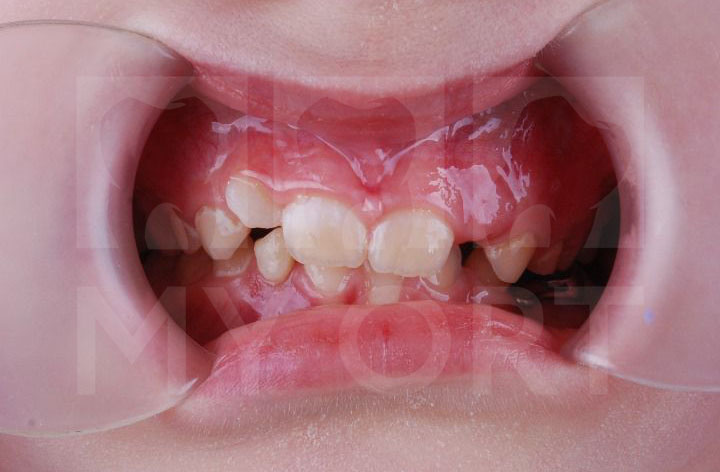

Родители семилетней девочки обратились ко мне, врачу-стоматологу, ортодонту, гнатологу, с жалобами на неправильный прикус. У ребенка начали прорезываться постоянные зубы и родителей беспокоило отсутствие места для нормального роста зубов.

Компьютерная томография (КТ) показала у ребенка — дистальный прикус, ретрузию и кант окклюзионной плоскости зубов.

Пациентка носила два эластичных корректора с перерывом.

Первая каппа дала слабовыраженный результат, это было связано с влиянием системного заболевания у девочки и проводимой терапии.

Через некоторое время мы начали лечение на каппе уже большего размера. Девочке уже был знаком опыт использования аппарата, и процесс проходил спокойнее (сама по себе девочка очень тревожная и трепетная).

Улыбка До и После

Посмотрите, что у нас получилось:

До и после